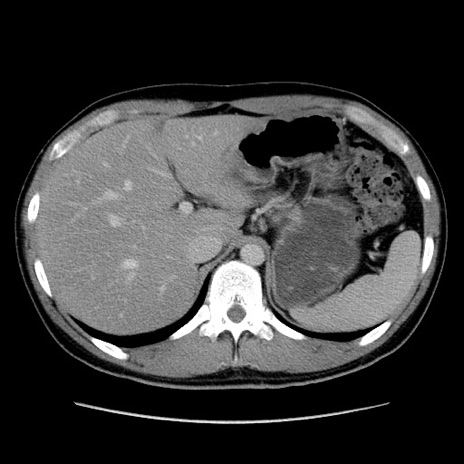

症例36(横断像)

【症例】20歳代 男性

【主訴】心窩部痛

【現病歴】今朝より上腹部痛あり。一旦軽快していたが再度出現したため救急要請。昨日夕に白身の魚を含む刺身を食べた。

【身体所見】BP 136/89mmHg、HR 74/min、BT 37.0℃、腹部:膨満、軟、心窩部に圧痛あり。反跳痛なし、筋性防御なし、腸雑音やや亢進あり。

【データ】WBC 17700、CRP 0.48